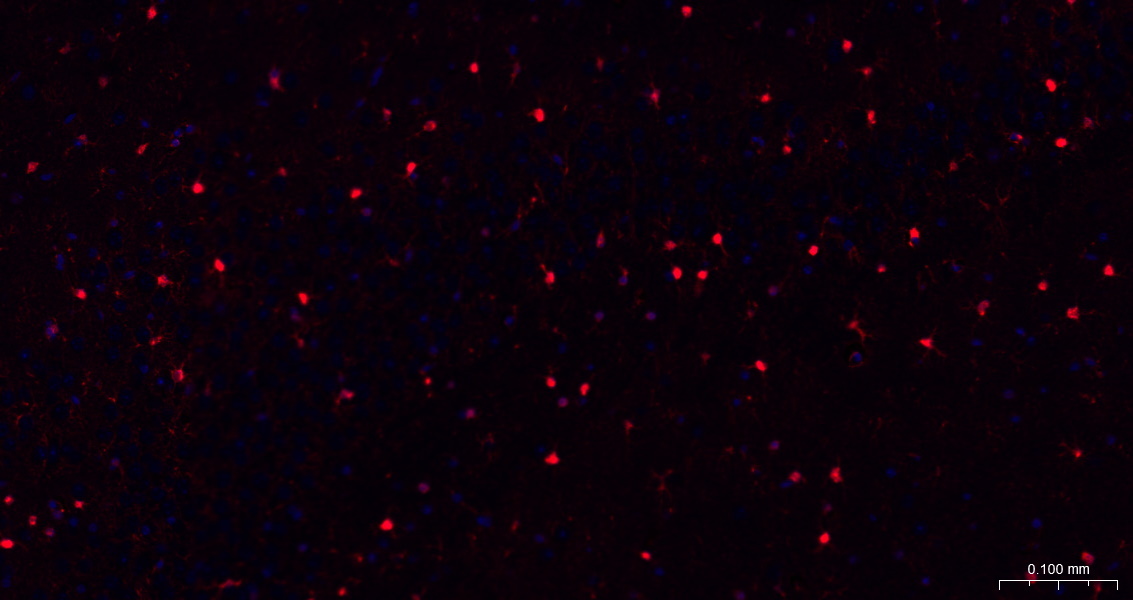

Paraformaldehyde-fixed, paraffin embedded Mouse Cerebrum; Antigen retrieval by boiling in sodium citrate buffer (pH6.0) for 15 min; The section was incubated with S100B Monoclonal Antibody, Unconjugated (bsm-52506R) at 1:200 overnight at 4°C. Followed by conjugated Goat Anti-Rabbit IgG antibody (Red, bs-0295G-BF594), DAPI (blue, C02-04002) was used to stain the cell nuclei.